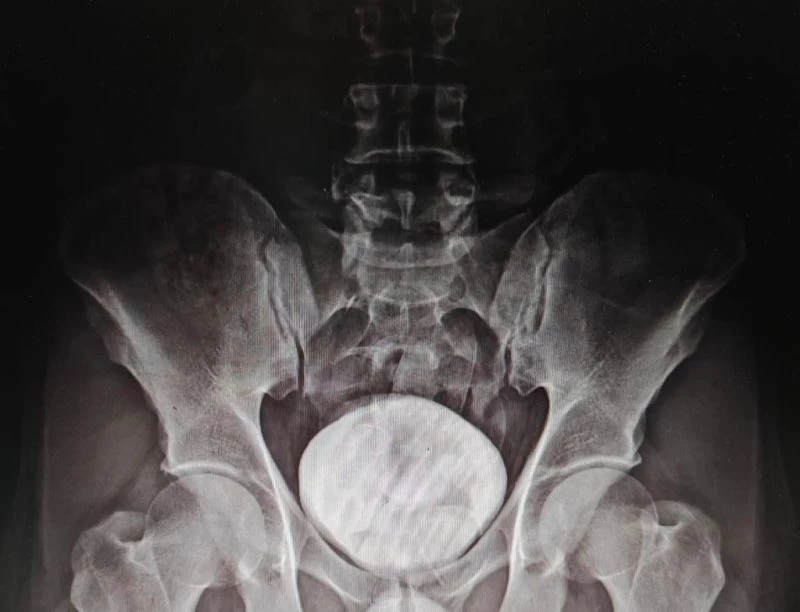

Polis yaptığı üst aramasında bir şey bulamayınca şüpheliyi Kars Harakani Devlet Hastanesine götürdü. Burada çekilen röntgen sonucu Mohammad Zadeh Tazehkand’ın mide ve bağırsaklarında kapsüller içerisinde 7 parça halinde 258,53 gram metamfetamin maddesi tespit etti.